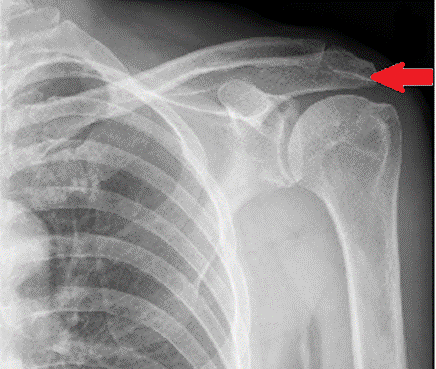

W jakiej projekcji i pod jakim kątem padania promienia centralnego został wykonany radiogram obojczyka?

Ilustracja do pytania 38

A. W projekcji PA i prostopadłym kącie padania promienia centralnego.

B. W projekcji AP i skośnym dołgłowowo kącie padania promienia centralnego.

C. W projekcji AP i prostopadłym kącie padania promienia centralnego.

D. W projekcji AP i skośnym doogonowo kącie padania promienia centralnego.